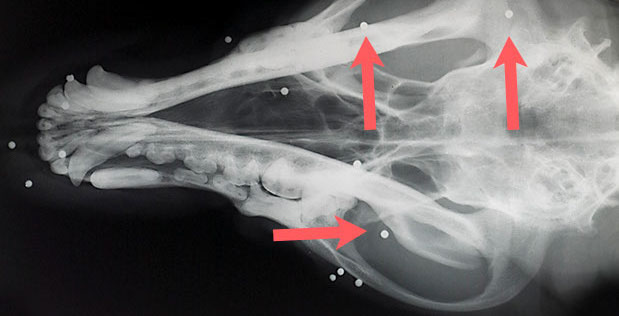

Schrotkugeln im Kopf eines Jagdhundes